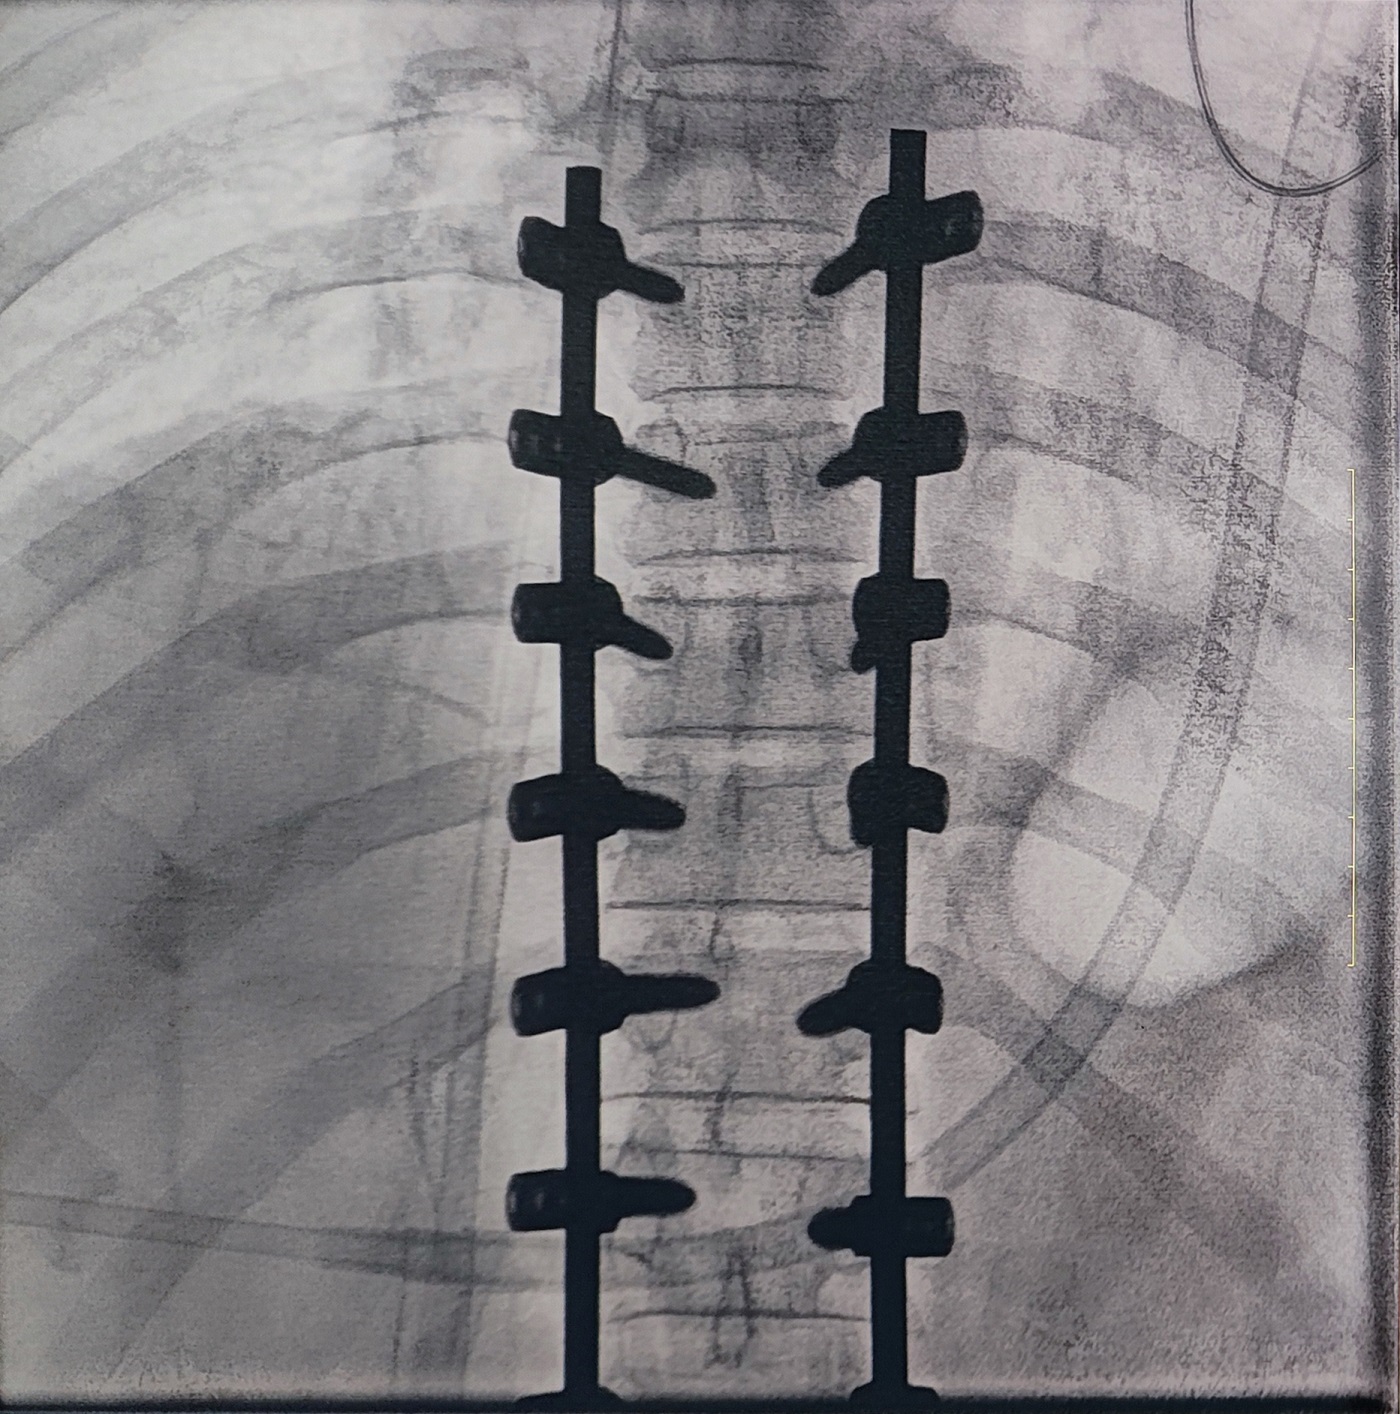

一場脊柱手術(shù)中,醫(yī)生需要拍攝跨越7個(gè)節(jié)段的脊柱影像,由于曝光的視野較大,常規(guī)視野的C形臂通常需要拍攝2-3次,普愛醫(yī)療大平板一體式C形臂30CM*30CM的“大視野”,輔助醫(yī)生一次性完成了7個(gè)節(jié)段的拍攝。最終,醫(yī)生在高清影像的輔助下完成了14枚螺釘?shù)木珳?zhǔn)定位、置入。

大視野,不僅意味著醫(yī)生可以更快,獲取更全面的影像信息,做出精準(zhǔn)判斷,無需多次拍攝定位,也顯著地降低了患者接受的輻射劑量,保護(hù)了患者的安全。